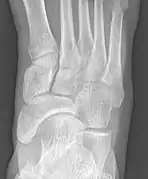

Radiological images

Type 2

Cornuate navicular bone